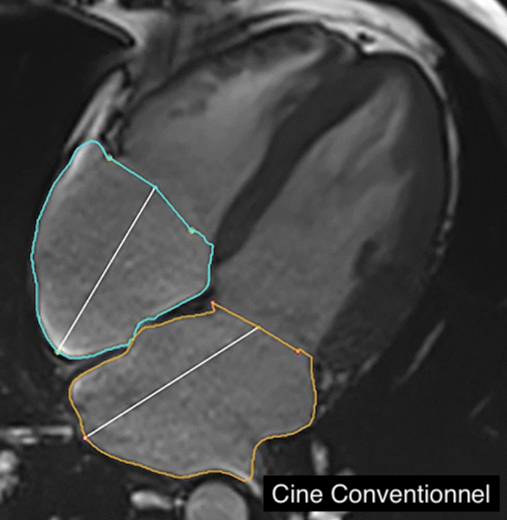

Une étude germano-américaine publiée dans la Revue European Radiology se propose de comparer les paramètres volumétriques et fonctionnels auriculaires cardiaques dérivées de séquences ciné basées sur le CS par rapport à l'imagerie ciné conventionnelle (Conv). Les chercheurs ont activé des séquences ciné CS et Conv chez 101 patients (82 volontaires sains (HV) et 19 patients souffrant d'insuffisance cardiaque avec fraction d'éjection réduite (HFrEF)) à l'aide d’une IRM 3T dans cette étude monocentrique. Une analyse temps-volume auriculaire gauche (LA) et droite (RA) a été réalisée dans les deux séquences pour évaluer les volumes et la fonction auriculaires.

L’étude a montré que les images basées sur le CS ont permis de réduire de 69% le temps d'acquisition. Une différence significative a été trouvée dans les paramètres auriculaires entre les cinés CS et Conv, notamment sur le volume minimal auriculaire (Conv 24,0 ml contre CS 25,7 ml). Cependant, l’expérience a montré une corrélation élevée entre les deux techniques. Les chercheurs en ont déduit que l'évaluation volumétrique et fonctionnelle auriculaire cardiaque utilisant l'imagerie ciné IRM Compressed Sensing est réalisable et reproductible avec une réduction significative du temps d'acquisition, renforçant ainsi le rôle du CS dans la CMR clinique pour l'imagerie auriculaire cardiaque.